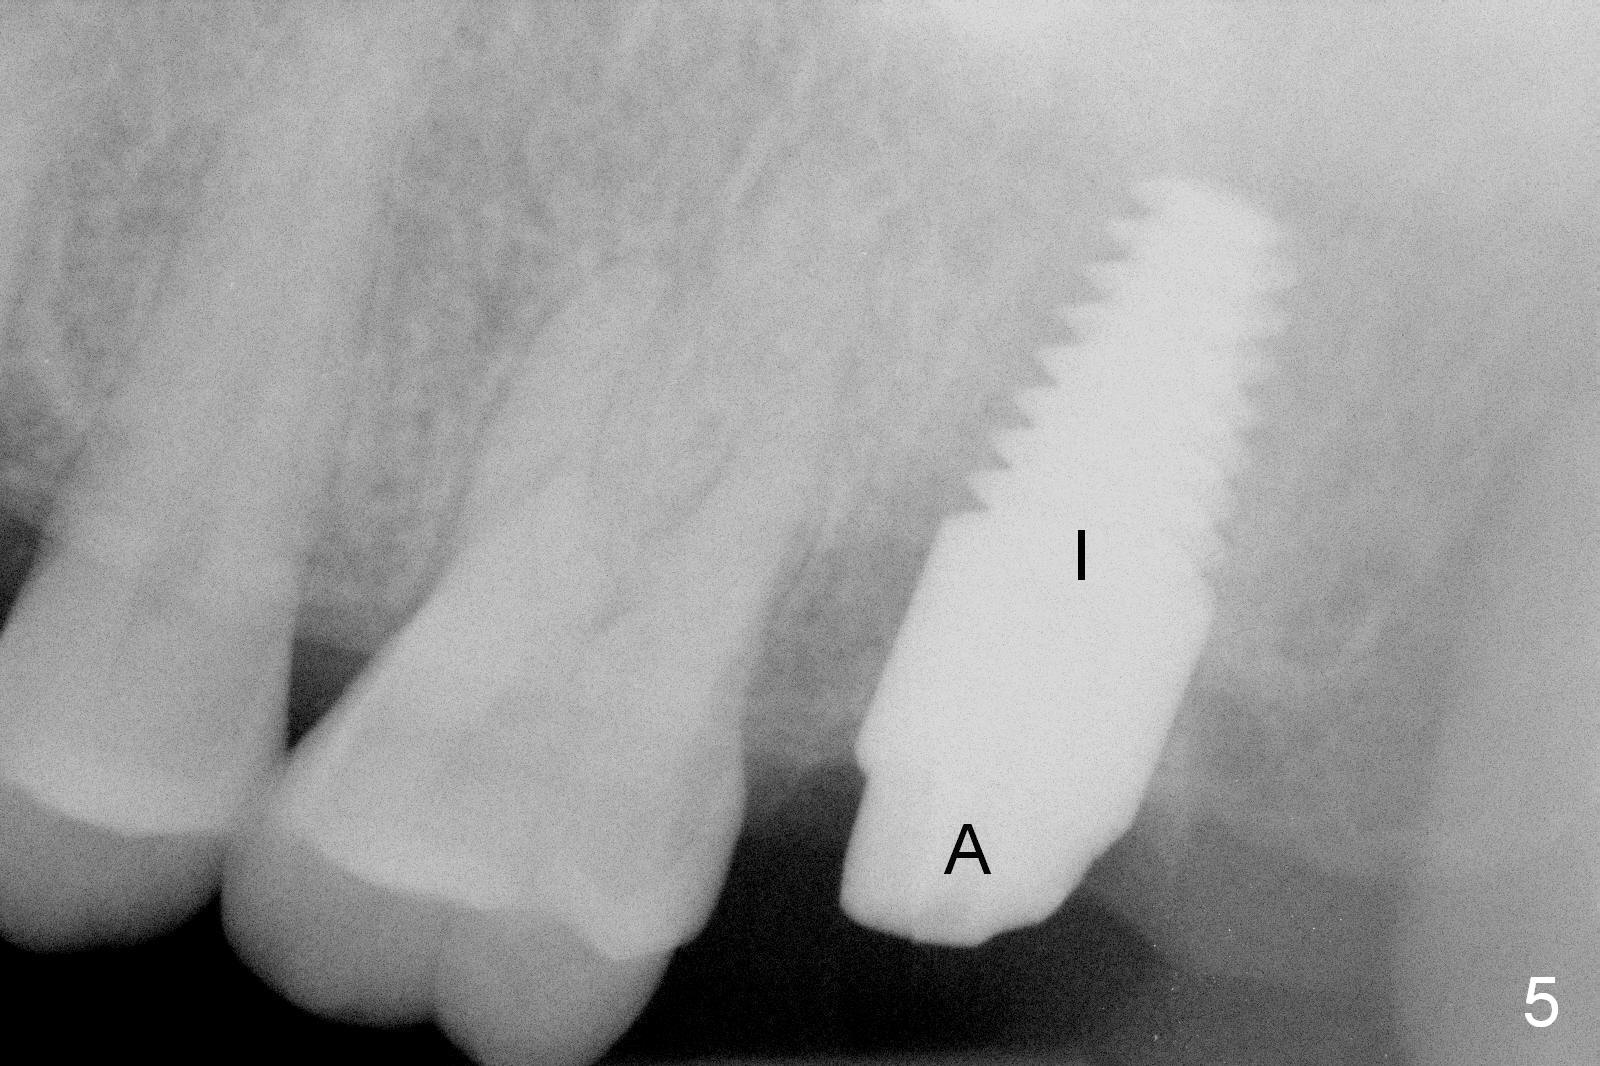

A 50-year-old man (TK) had sign & symptom of crack tooth at #15 (Fig.1) and chose to have root canal therapy done by a specialist. One month later, he returns for crown; exam reveals a crack line mesiodistally (Fig.2). The patient agrees to have immediate implant (Fig.3 design: 6x14 mm). The buccal roots fracture upon luxation. Osteotomy starts in the septum with a 2 mm pilot drill and deviates to the palatal socket, followed by 2, 3, 4 mm tapered osteotomes. A series of taps are placed: 6x17 mm one achieves stability (Fig.4). When the latter is removed, there is no sign of sinus air leakage. A 6x14 mm implant (Fig.5 I) and a 5x3 mm abutment (A) are placed. After abutment height adjustment, an immediate provisional is fabricated. Allograft with Osteogen is placed in the remaining sockets and gaps (Fig.6 *). Fig.7 shows the inner side of the provisional with double arrows indicating the dimension of the abutment, whereas arrowheads the dimension of the socket buccopalatally. When the provisional is cemented (Fig.8 P), it completely seals the socket. As long as the provisional stays, bone graft will not be lost.